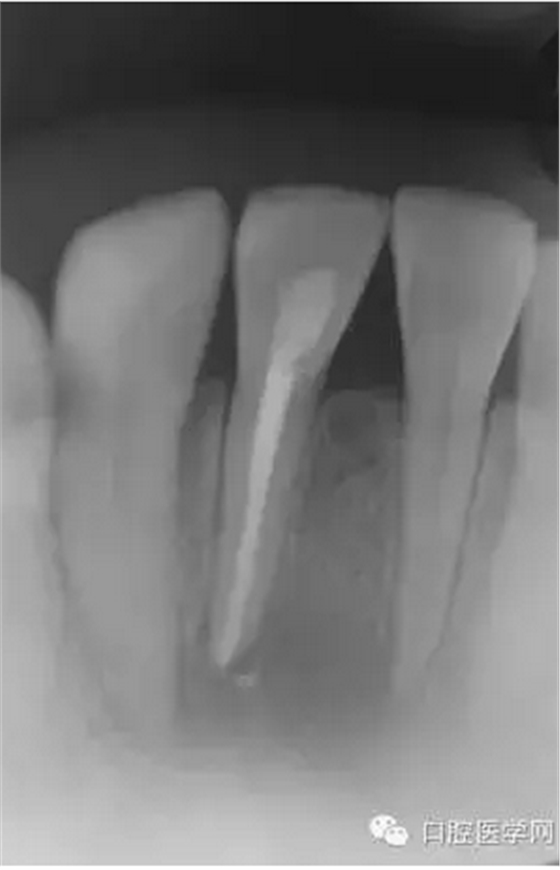

根管充填1個(gè)月后復(fù)診檢查過之后,一年后再次復(fù)診。如(圖5),可見大范圍破壞根尖周病變大部分基本治愈。

(圖 4) 根管充填1個(gè)月后

(圖 5) 根管充填約1年后